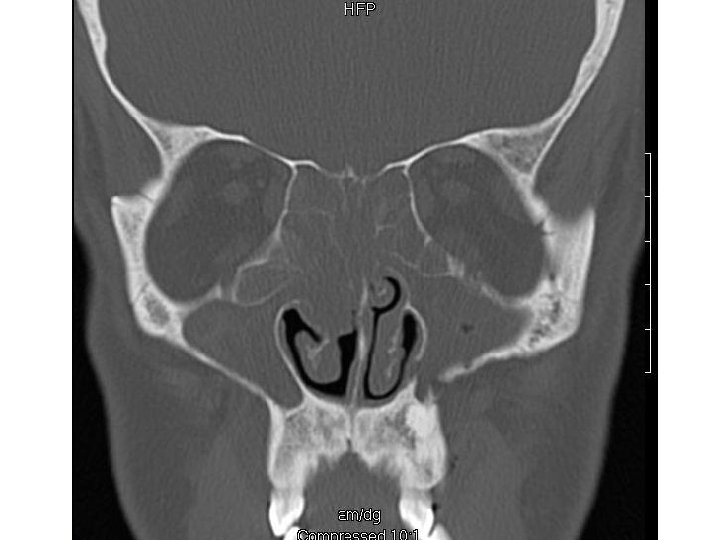

Ethmoid Sinusitis

Coronal computed tomographic scan showing ethmoidal polyps. Ethmoid opacity is total as a result of nasal polyps, with a secondary fluid level in the left maxillary antrum.